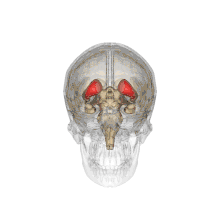

Caudate nucleus

![]() Caudate nucleus (in red) shown within the brain | |

Caudate nuclei along with other subcortical structures, in glass brain